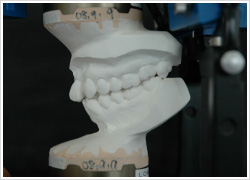

当院では初診時の検査で、ほとんどの患者さんで術者が複数のかみ合わせの記録を取って、それを使って咬合器に歯列模型を装着して、患者さん本来の正しい咬み合わせの位置と患者さんが自然と咬み合わせた位置の差を目に見える形で明らかにして診断を行っていきます。顎関節症が進行した方では顎関節部のCT撮影やMRI撮影を提携医療機関にて撮影していただき、その状態を把握することも行っています。単に歯並びを治したいだけなのにCT撮影やMRI撮影を行うのは大袈裟に感じるかもしれませんが、会話や咀嚼などの口腔の機能を正しく行うために顎関節はその要になる部位であり、その状態をできるだけ詳細に知ったうえで診断を行い、治療計画に反映させることが大切だからです。歯並びや咬み合わせの改善だけでなく、顔貌の改善や歯の周囲の歯肉や骨を健康に保つためにも顎関節の状態は軽視できません。

患者さんの習慣的な顎位と本来の正しい顎位の差を見るためのデータです。このずれがどれくらいあるか、検査の後の診断時にお示しします。